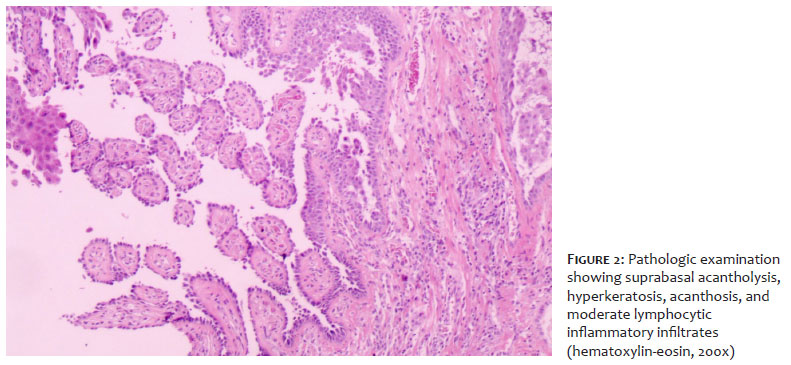

A 50-year-old male patient, White, previously diagnosed with pemphigus vulgaris, had bullous lesions on his nose, scalp, oral mucosa, trunk, abdomen, arms, and legs. A laboratory assessment found no relevant alterations. The initial therapeutic options were prednisone, azathioprine, and mycophenolate, but they had to be discontinued due to their side effects. Except for the lesions on the patient's scalp, which progressed to a vegetative appearance, all other lesions were controlled by using rituximab (Figure 1A and 1B). Pathologic examination of the scalp lesion found suprabasal acantholysis, hyperkeratosis, acanthosis, and moderate lymphocytic inflammatory infiltrates (Figure 2). Direct immunofluorescence found IgG positivity, with intercellular pattern in the epidermis. Clinical-histological correlation corroborated the diagnosis of pemphigus vegetans. The choice was made to administer botulinum toxin as an experimental treatment for the scalp lesions. After topical application of 4% lidocaine cream (Dermomax®) on the scalp plaques for 30 minutes and antisepsis with 0.2% aqueous chlorhexidine, botulinum toxin type A (Botox®), 2 UI/cm2, was injected intradermally (Table 1). After 6 weeks, lesion verrucosity had improved by over 50%. At reassessment, a new dose of botulinum toxin was administered, following the same procedure, achieving progressive improvement (Figure 3A and 3B).